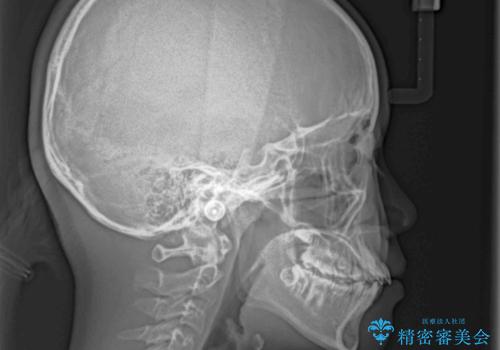

- 八重歯と乳歯が残っていることを気にして来院された患者様です。

乳歯が3歯残っており、下顎は左右ともに後続永久歯がない状態でした。

口元が突出しており、口が閉じにくかったため、乳歯を含め上下5歯を抜歯して矯正治療を行うこととしました。

下顎の乳歯は永久歯と比べて幅が大きいため、抜歯した場合のスペースが大きく、治療には長期間を要することが一般的です。

今回の患者様は中学生ということもあり、成人の患者様と比べ動きが速く、2年間で治療を終えることができました。